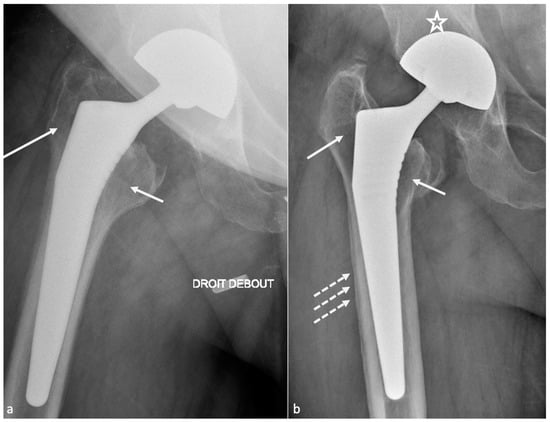

4.1. Dislocation

4.1.2. Imaging

4.1.3. Imaging Perspectives